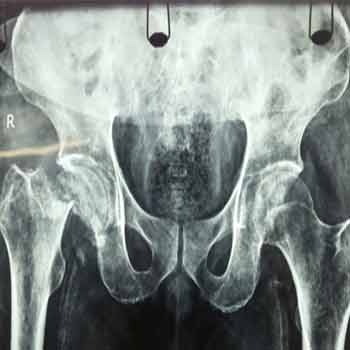

Case:8 Polytrauma

Patient having closed segmented fracture midshaft & lower 1/3 Tibia with closed fracture superior & inferior pubic rami right side with pelvis fracture following vehicular accident wastreated with intramedullary nail for fracture tibia and external fixator for fracture pelvis.

Pre-Op

Immdiate Post-op

Post-op Lateral

Ex fix with frame